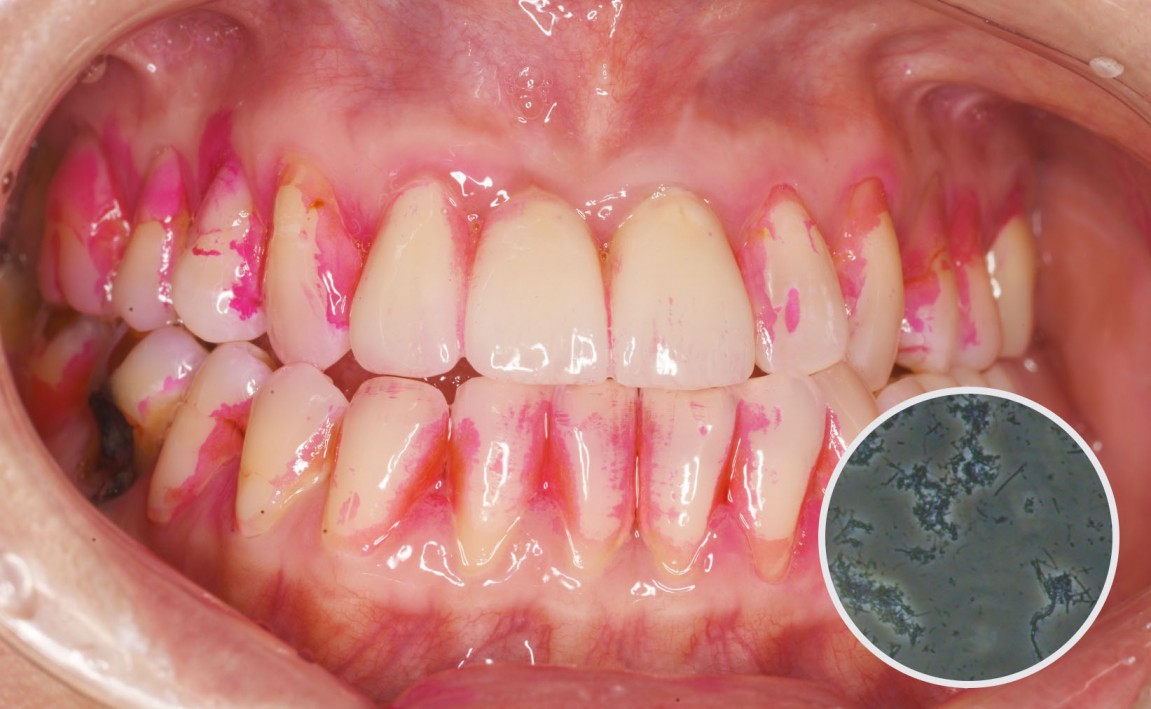

전.jpg

치료전 : 2023-06-19